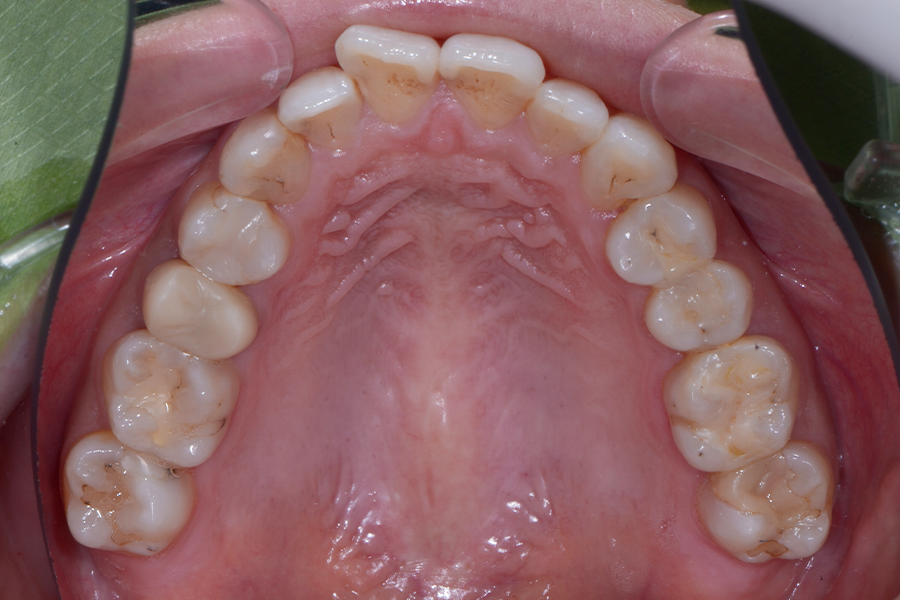

• 治療後